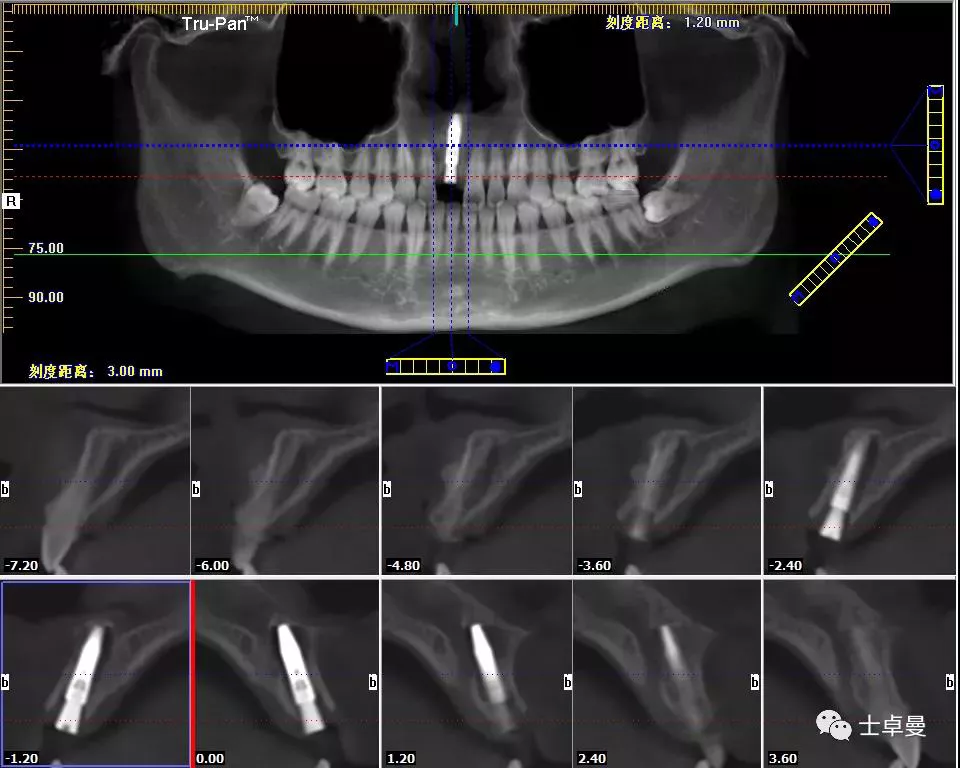

影像学检查,CBCT显示

· 11根管内充填致密,根尖未见明显阴影,根长约12mm;

· 唇侧牙槽骨完整,厚度约1.2mm;

· 根尖区剩余骨量约7mm。

术后即刻CT示,种植体植入位置理想